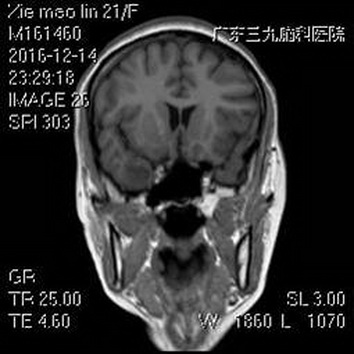

毁损术后MR